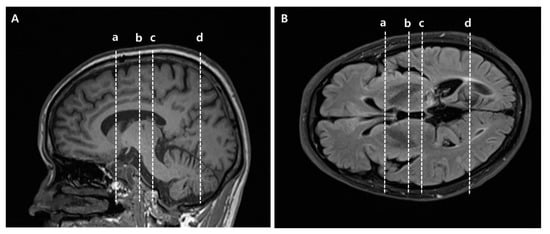

The normalized FA values of STT in the CPSP group were lower than those in the stroke control group and normal control groups; 0.79 for CPSP, 0.98 for non-CPSP, 0.98 for control (Figure 2A). The normalized FA values of STR in the CPSP group were lower than those in the stroke control group and normal control groups; 0.88 for CPSP, 1.00 for non-CPSP, 0.97 for control (Figure 2B). There were no differences in the FA values of STT and STR between the stroke control and normal control groups. The normalized FN values of STT and STR were lower in the CPSP and stroke control group than in the normal control group. However, there was no significant difference between the CPSP and stroke control for the normalized FN of STT and STR. Representative DTIs of STT in all three groups are shown in Figure 3, and those of STR in Figure 4.

Figure 3. Representative diffusion tensor tractography images of the spinothalamic tract in typical subjects from the (A) CPSP, (B) stroke control, and (C) normal control groups. The non-affected tract is shown in red, and the affected tract in yellow.